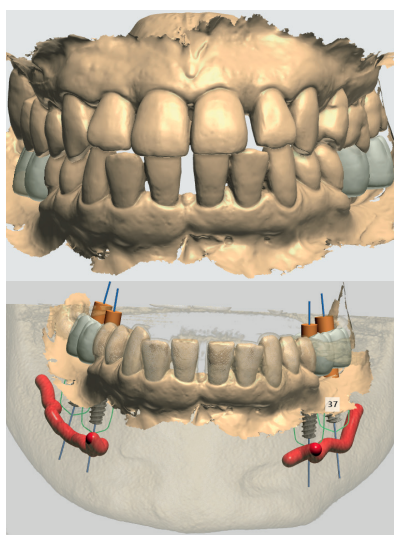

Paciente mujer de 55 años que acude a la consulta para rehabilitar protésicamente sectores posteriores (Figura 1). A nivel oral presenta patología dental y periodontal además de las ausencias de molares. Con necesidad de tratamiento quirúrgico, periodontal y restaurador (Figura 2).

A nivel odontológico el diagnóstico y el tratamiento de la paciente presenta patología dental y periodontal además de las ausencias dentarias. Se realizaron obturaciones, tratamiento periodontal básico y quirúrgico, extracciones dentarias, rehabilitación con prótesis fija y tratamiento rehabilitador con implantes dentales (Figura 3).